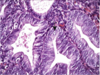

Complete hydatidiform mole

villous enlargement, edema, and circumferential trophoblast proliferation

Complete hydatidiform mole

SNOWSTORM

Partial hydatidiform mole

villi: some normal, others swollen, avascular and grape-like

minimal trophoblastic proliferation

Complete hydatifiform mole

grape-like

Partial hydatidiform mole